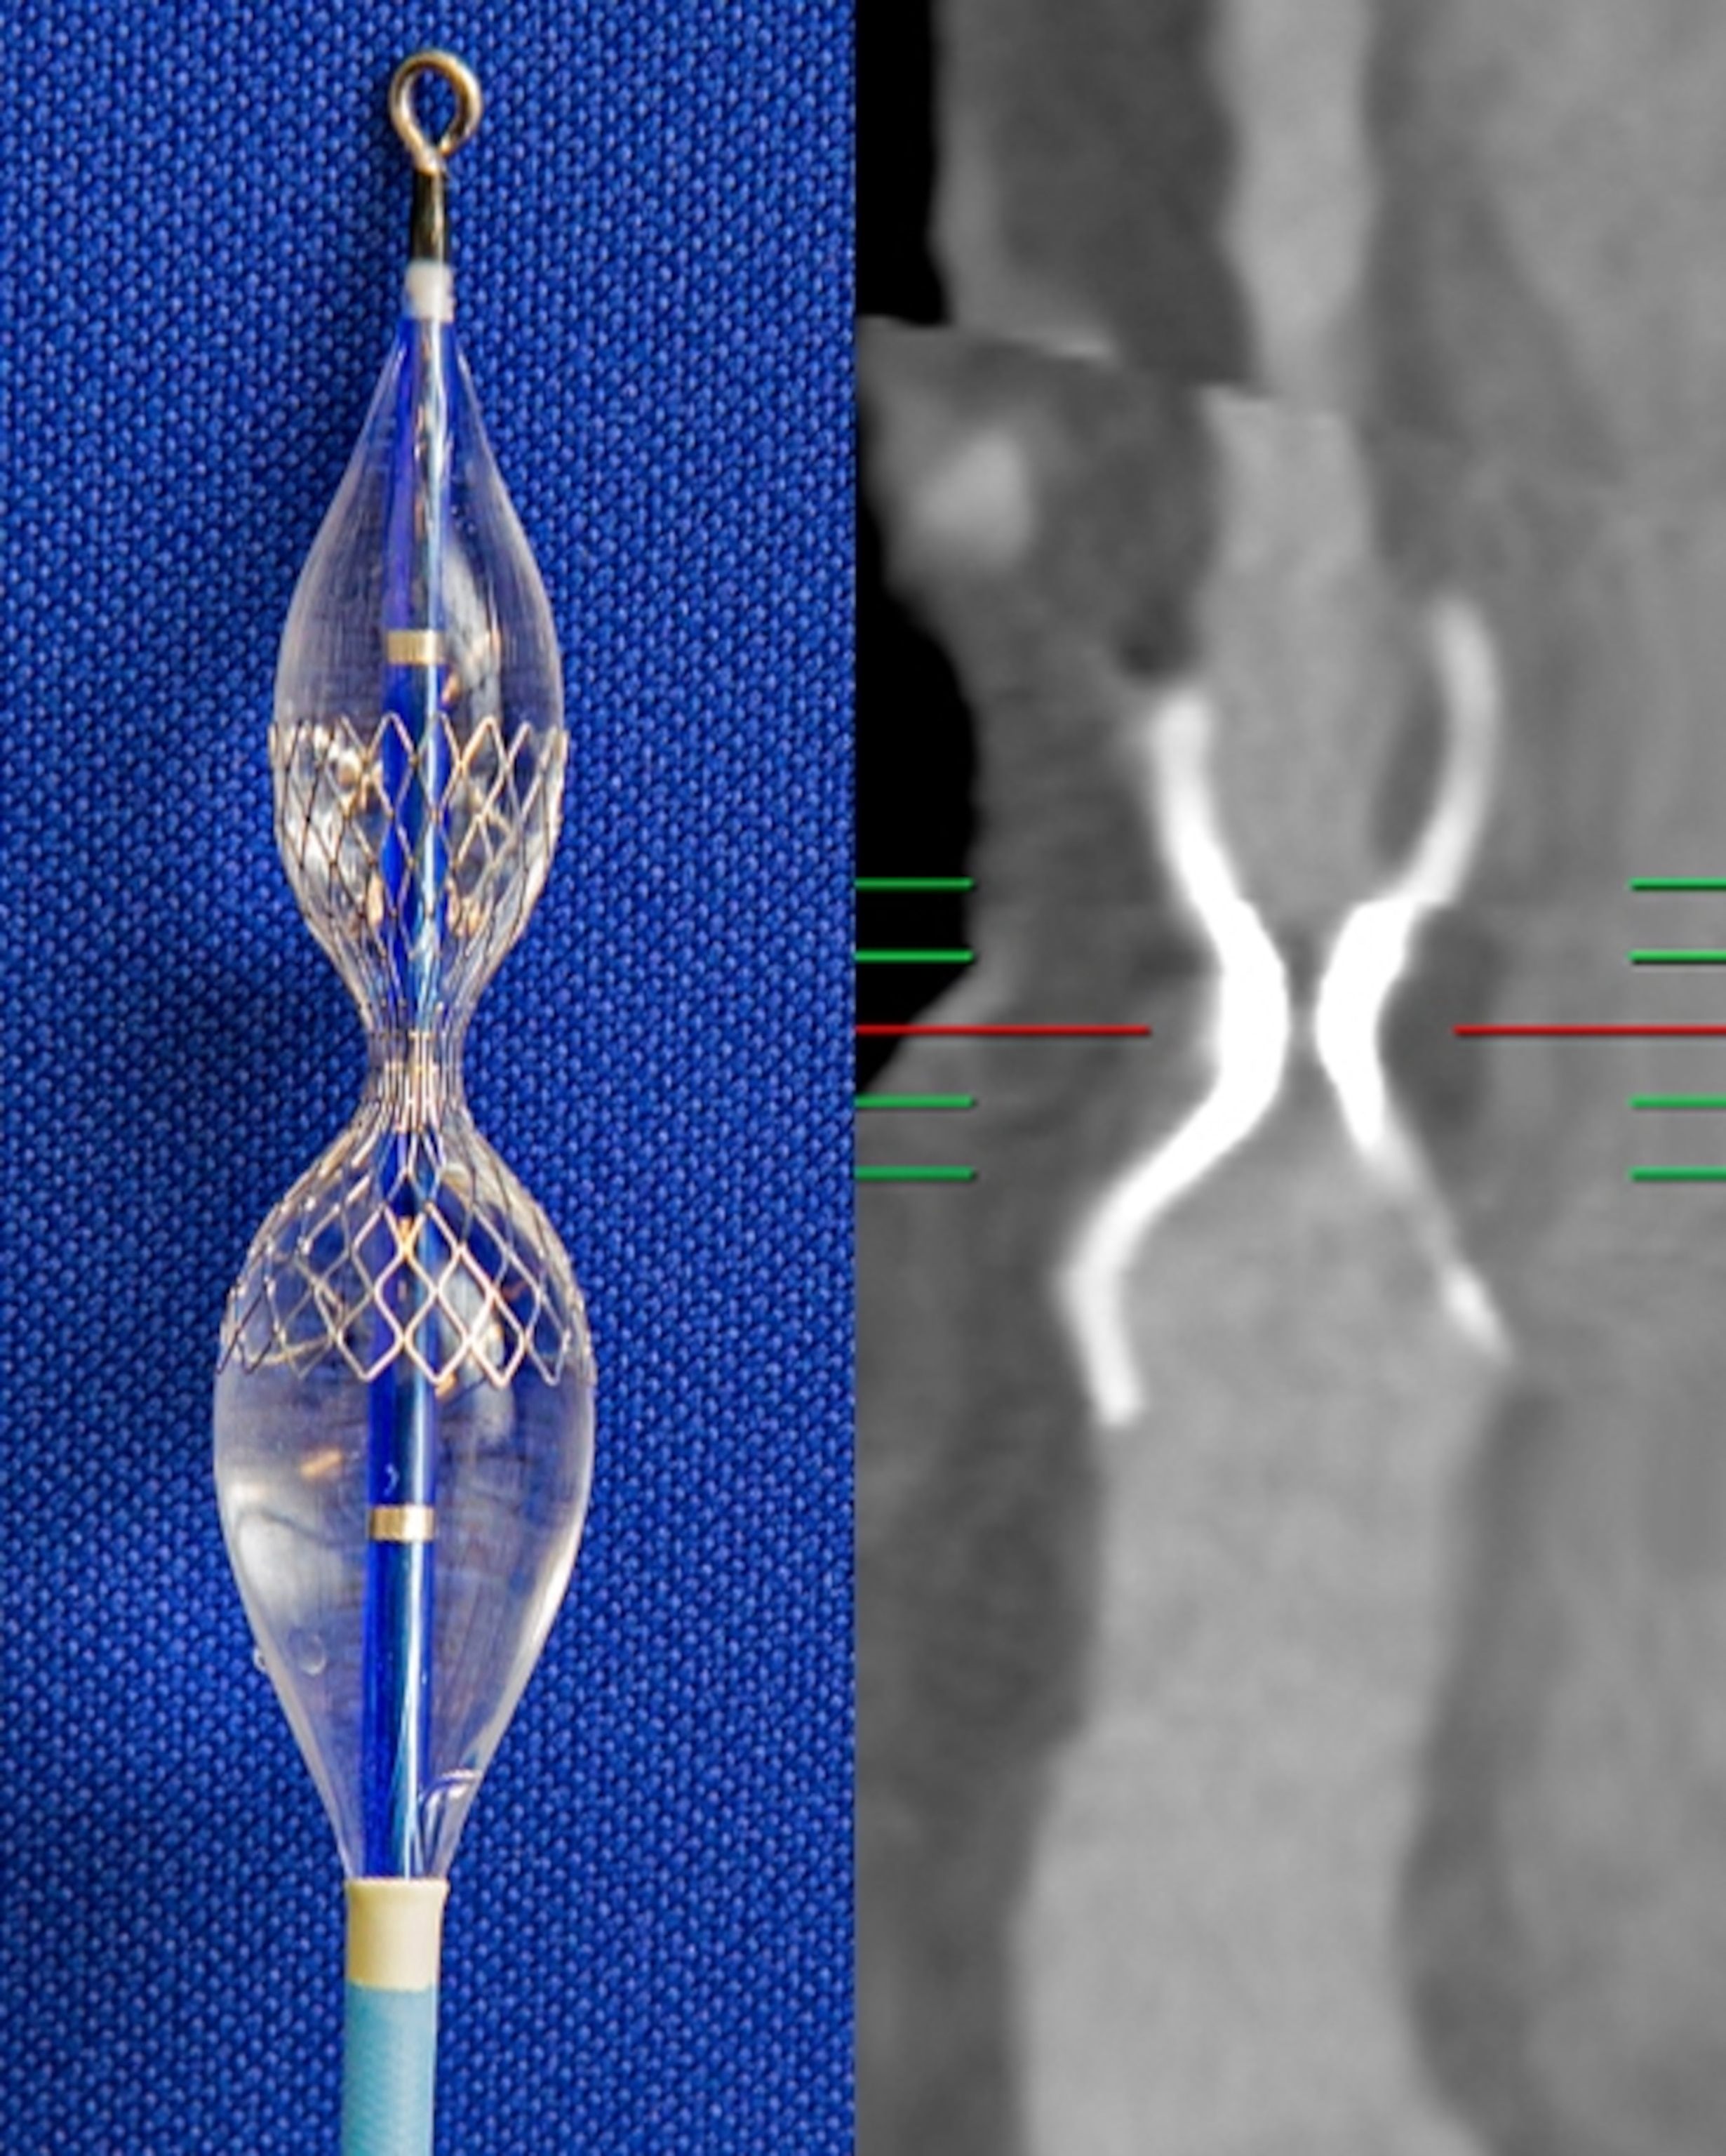

Our perception of pain isn’t limited to merely sensing it. The feelings of unpleasantness, fear, and anxiety that accompany the sensation are an integral part of experiencing pain. In a trial at the Cleveland Clinic, researchers led by neurosurgeon Andre Machado used deep brain stimulation (DBS) to target this emotional component of pain in 10 patients who had chronic neuropathic pain after suffering a stroke. The researchers implanted tiny electrodes in a part of the brain involved in processing emotions. Wired to an electronic device inserted in the chest, the electrodes delivered mild shocks to the implantation site at a rate of nearly 200 a second.